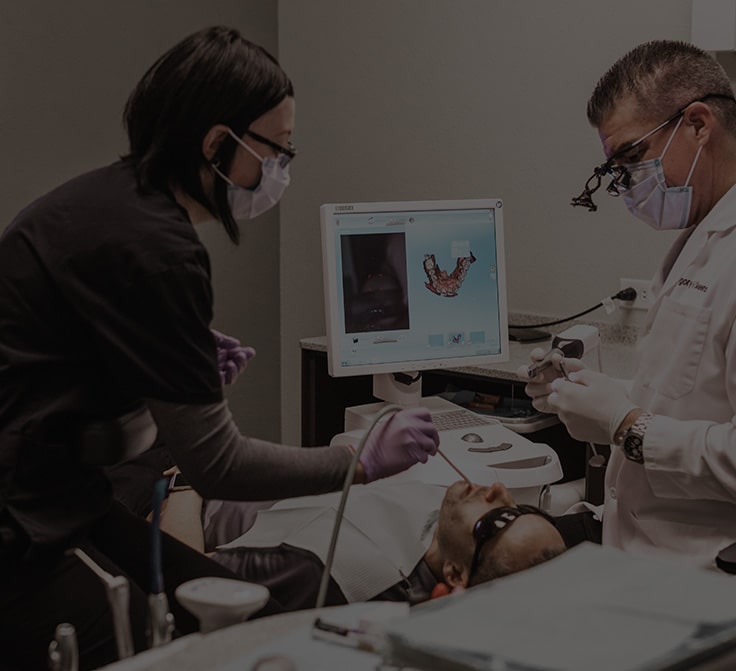

How Does My Dentist Take a Digital Impression?

Have you ever had a mold made of your teeth? The gooey impression material filling your mouth, or even tickling the back of your throat? If you have a sensitive gag reflex, you probably remember the sensation quite well. Fortunately, digital dental impressions (near you) are changing the way our patients undergo routine restorative treatments […]